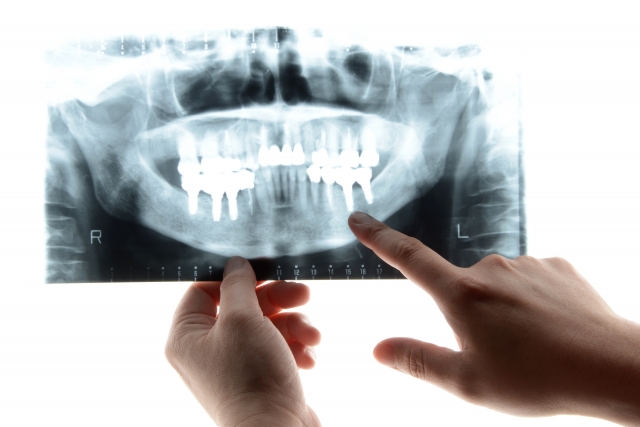

子どもにインプラントはできない?

- 予防

子どもにもインプラント治療は可能...

- 歯科治療の安全性